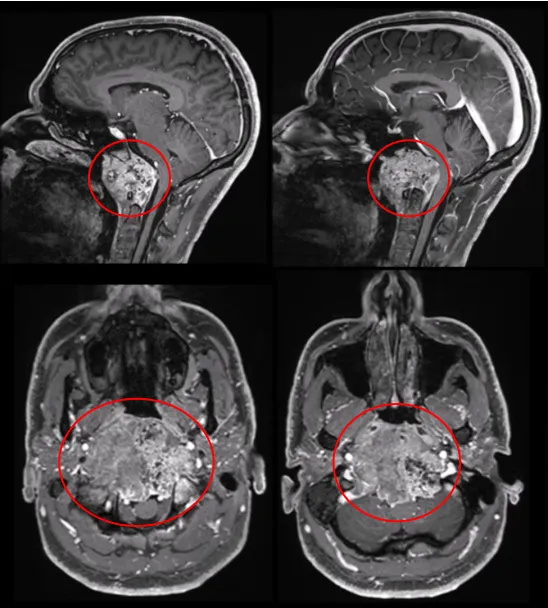

同样是脊索瘤,我们在福教授所治疗的另一个患者身上,也许能找到答案。肿瘤最大直径达10cm、瘤体积96.5cm³,巨大的肿瘤压迫脑干,福教授是如何做的?术后进行放疗了吗?

术前MRI显示,肿瘤呈浸润性生长,并向双侧后外侧扩展,右侧受累尤为严重。肿瘤侵袭至椎前间隙、下斜坡、双侧枕骨髁、第一颈椎C1的前弓以及C2的齿状突。

一整套综合治疗的结果如何?无并发症,他的肿瘤得到了完全切除。在术后恢复中,患者的吞咽功能得到显著改善,颈部疼痛也同步缓解。8周后,他接受了质子治疗。

术后MR显示,肿瘤已完全切除,对脑干和延髓的占位性压迫得到解除。